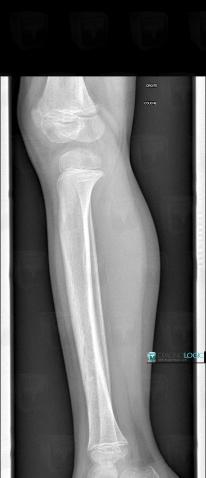

Fracture, Tibia - Mid part, X rays

Here is the specific information in the key image above:

- Diagnosis Fracture, Location(s) Tibia - Mid part, with gamuts